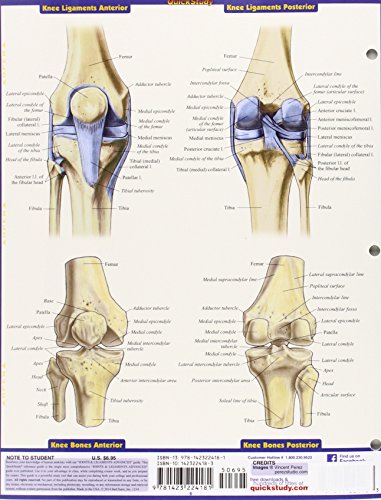

Joints & Ligaments Advanced QuickStudy Laminated Reference Guide (Quick Study Academic)